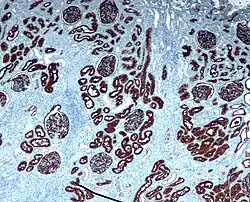

Иммуногистохими́ческое иссле́дование (ИГХ)— метод микроскопического исследования тканей, обеспечивающий наиболее специфическое выявление в них искомых веществ и основанный на обработке срезов маркированными специфическими антителами к выявляемому веществу, которое в данной ситуации служит антигеном[1]. Впервые способ окрашивания клеточных и тканевых компонентов с помощью специфических антител для микроскопического исследования был предложен A. Coons и соавторами в 1941 году; позднее были разработаны антитела, помеченные не флуоресцентными красителями, а ферментами.

- идентификация клеток различных типов по их уникальным маркерным признакам (имеет клиническое значение при дифференцировке гистологического типа опухолей молочной железы, щитовидной железы, лимфом и проч. опухолей; дифференцировке первичного очага опухолей при метастазировании);